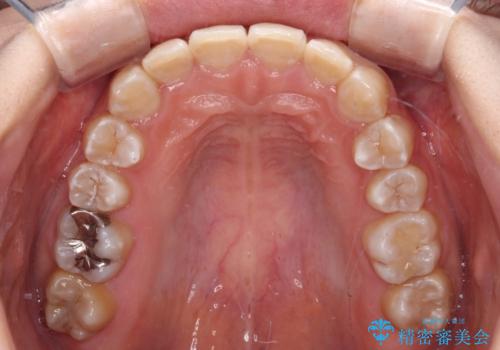

- 犬歯のクロスバイトを気にして来院された患者様です。

マウスピース矯正とワイヤー矯正の両方を提案しましたが、インビザラインの自己管理が煩わしいとのことで、ワイヤー装置による矯正治療を行うこととしました。

犬歯は歯根が太くて長いため、クロスバイトを改善するのは大変であることが多いですが、比較的スムーズに改善することができました。

インビザラインであったら、もっと期間はかかっていたような印象です。